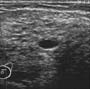

Ganglions intramammaires :

Dans les régions externes surtout.

Lacune hypoéchogène avec classiquement un centre hyperéchogène (sinus).